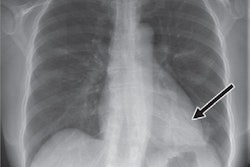

The group, led by Ulas Bagci, PhD, from the University of Central Florida, designed a 3D convolutional neural network to spot lung nodules of all expected sizes automatically, without the need for a user to guide the detection process. Called S4ND, the algorithm can find small nodules on CT scans, which radiologists often have a difficult time identifying, the authors noted.

They tested S4ND on nearly 1,000 chest CT scans from the Lung Nodule Analysis 2016 (LUNA16) dataset and found that it outperformed current detection methods. S4ND achieved an average score of 0.897 on a competition performance metric of accuracy and 95.2% sensitivity.